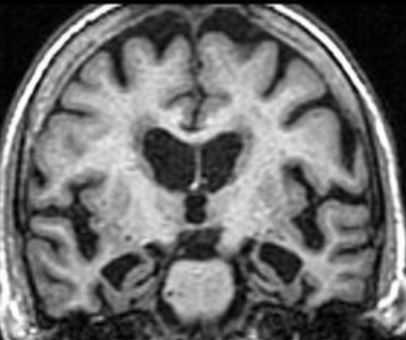

МРТ головного мозга выявляет скопление гемосидерина. Наиболее чувствительны градиентные Т2-взвешенные МРТ. Часто отмечается атрофия червя мозжечка, особенно, видимая хорошо на сагиттальных Т1-взвешенных МРТ.

МРТ головного мозга. Т2-взвешенная аксиальная МРТ через ствол. Тонкое темное кольцо гемосидерина вокруг ствола и в мозжечке. Сидероз головного мозга.